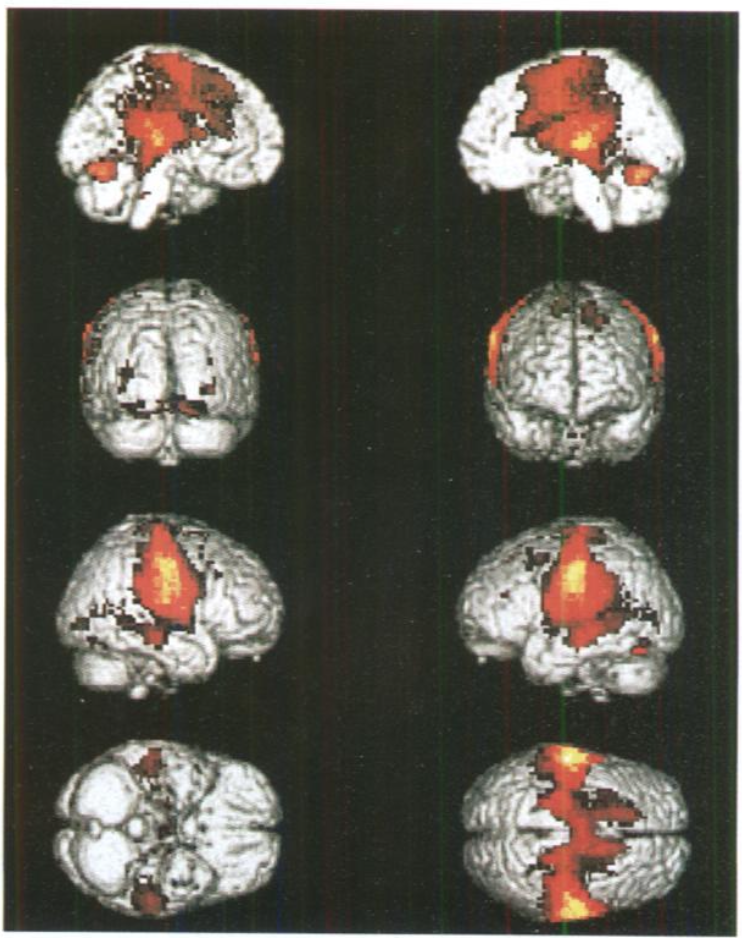

此外北大心理学系的一项研究显示,咀嚼口香糖显著增加了一些脑区的血流和供氧水平,所以能够起到调节情绪的作用[6]。

比如大脑的「扣带回」,就是参与情绪和认知等高级活动的,而嚼口香糖恰好激活了它。

研究者用核磁共振,观察了休息 VS 嚼口香糖时大脑的活动。

图片来源:参考文献 [6]